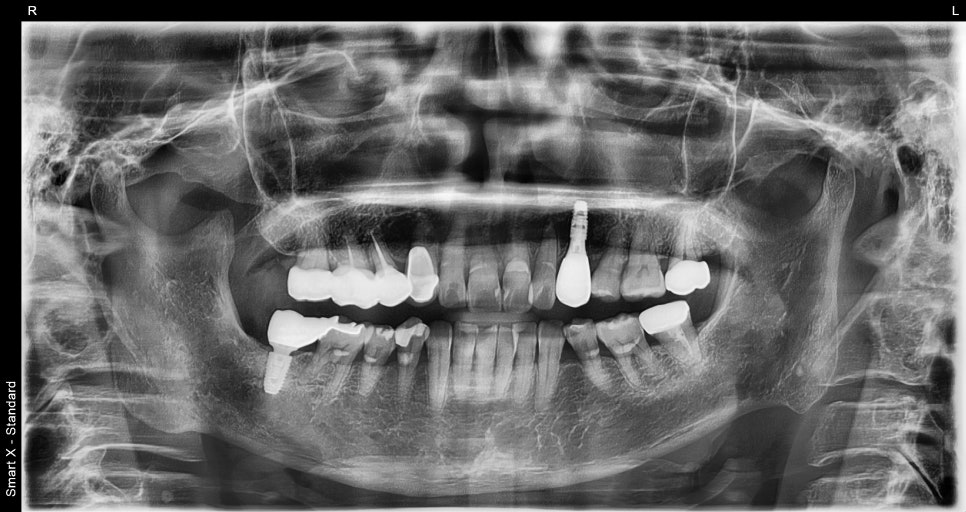

📸 Final panoramic X-ray

Panoramic photo after completion of the front tooth implant

📸 Panoramic X-ray immediately after surgery

Panoramic X-ray immediately after implant placement following osteomyelitis treatment

After confirming that the fixture (the implant root) was well positioned in the jawbone,

we fabricated a front tooth prosthesis that blended well with the natural teeth.